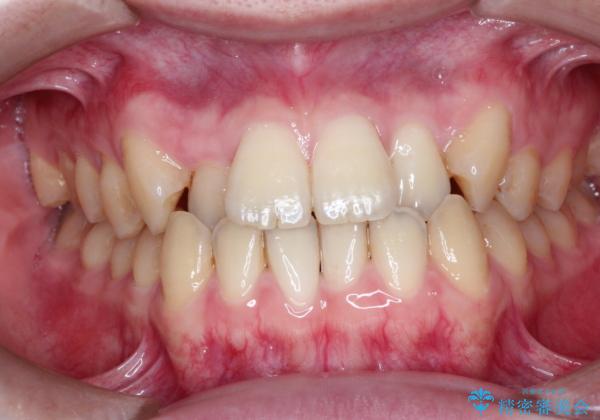

前歯のデコボコ インビザラインによる目立たない矯正

- 前歯のデコボコを主訴に来院された患者様です。

目立たないそうちをご希望されたので、インビザラインにて治療することとしました。

歯と歯の間をわずかに削ってスペースをつくり、デコボコを改善しました。